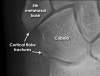

Cf) Flake fractures

Small flakes of bone are a common finding following trauma. The significance of these injuries depends on their anatomical location.

The fracture of 5th metatarsal base shown here is at the insertion point of the peroneus brevis tendon and is therefore potentially more significant than the fracture of the cuboid bone.